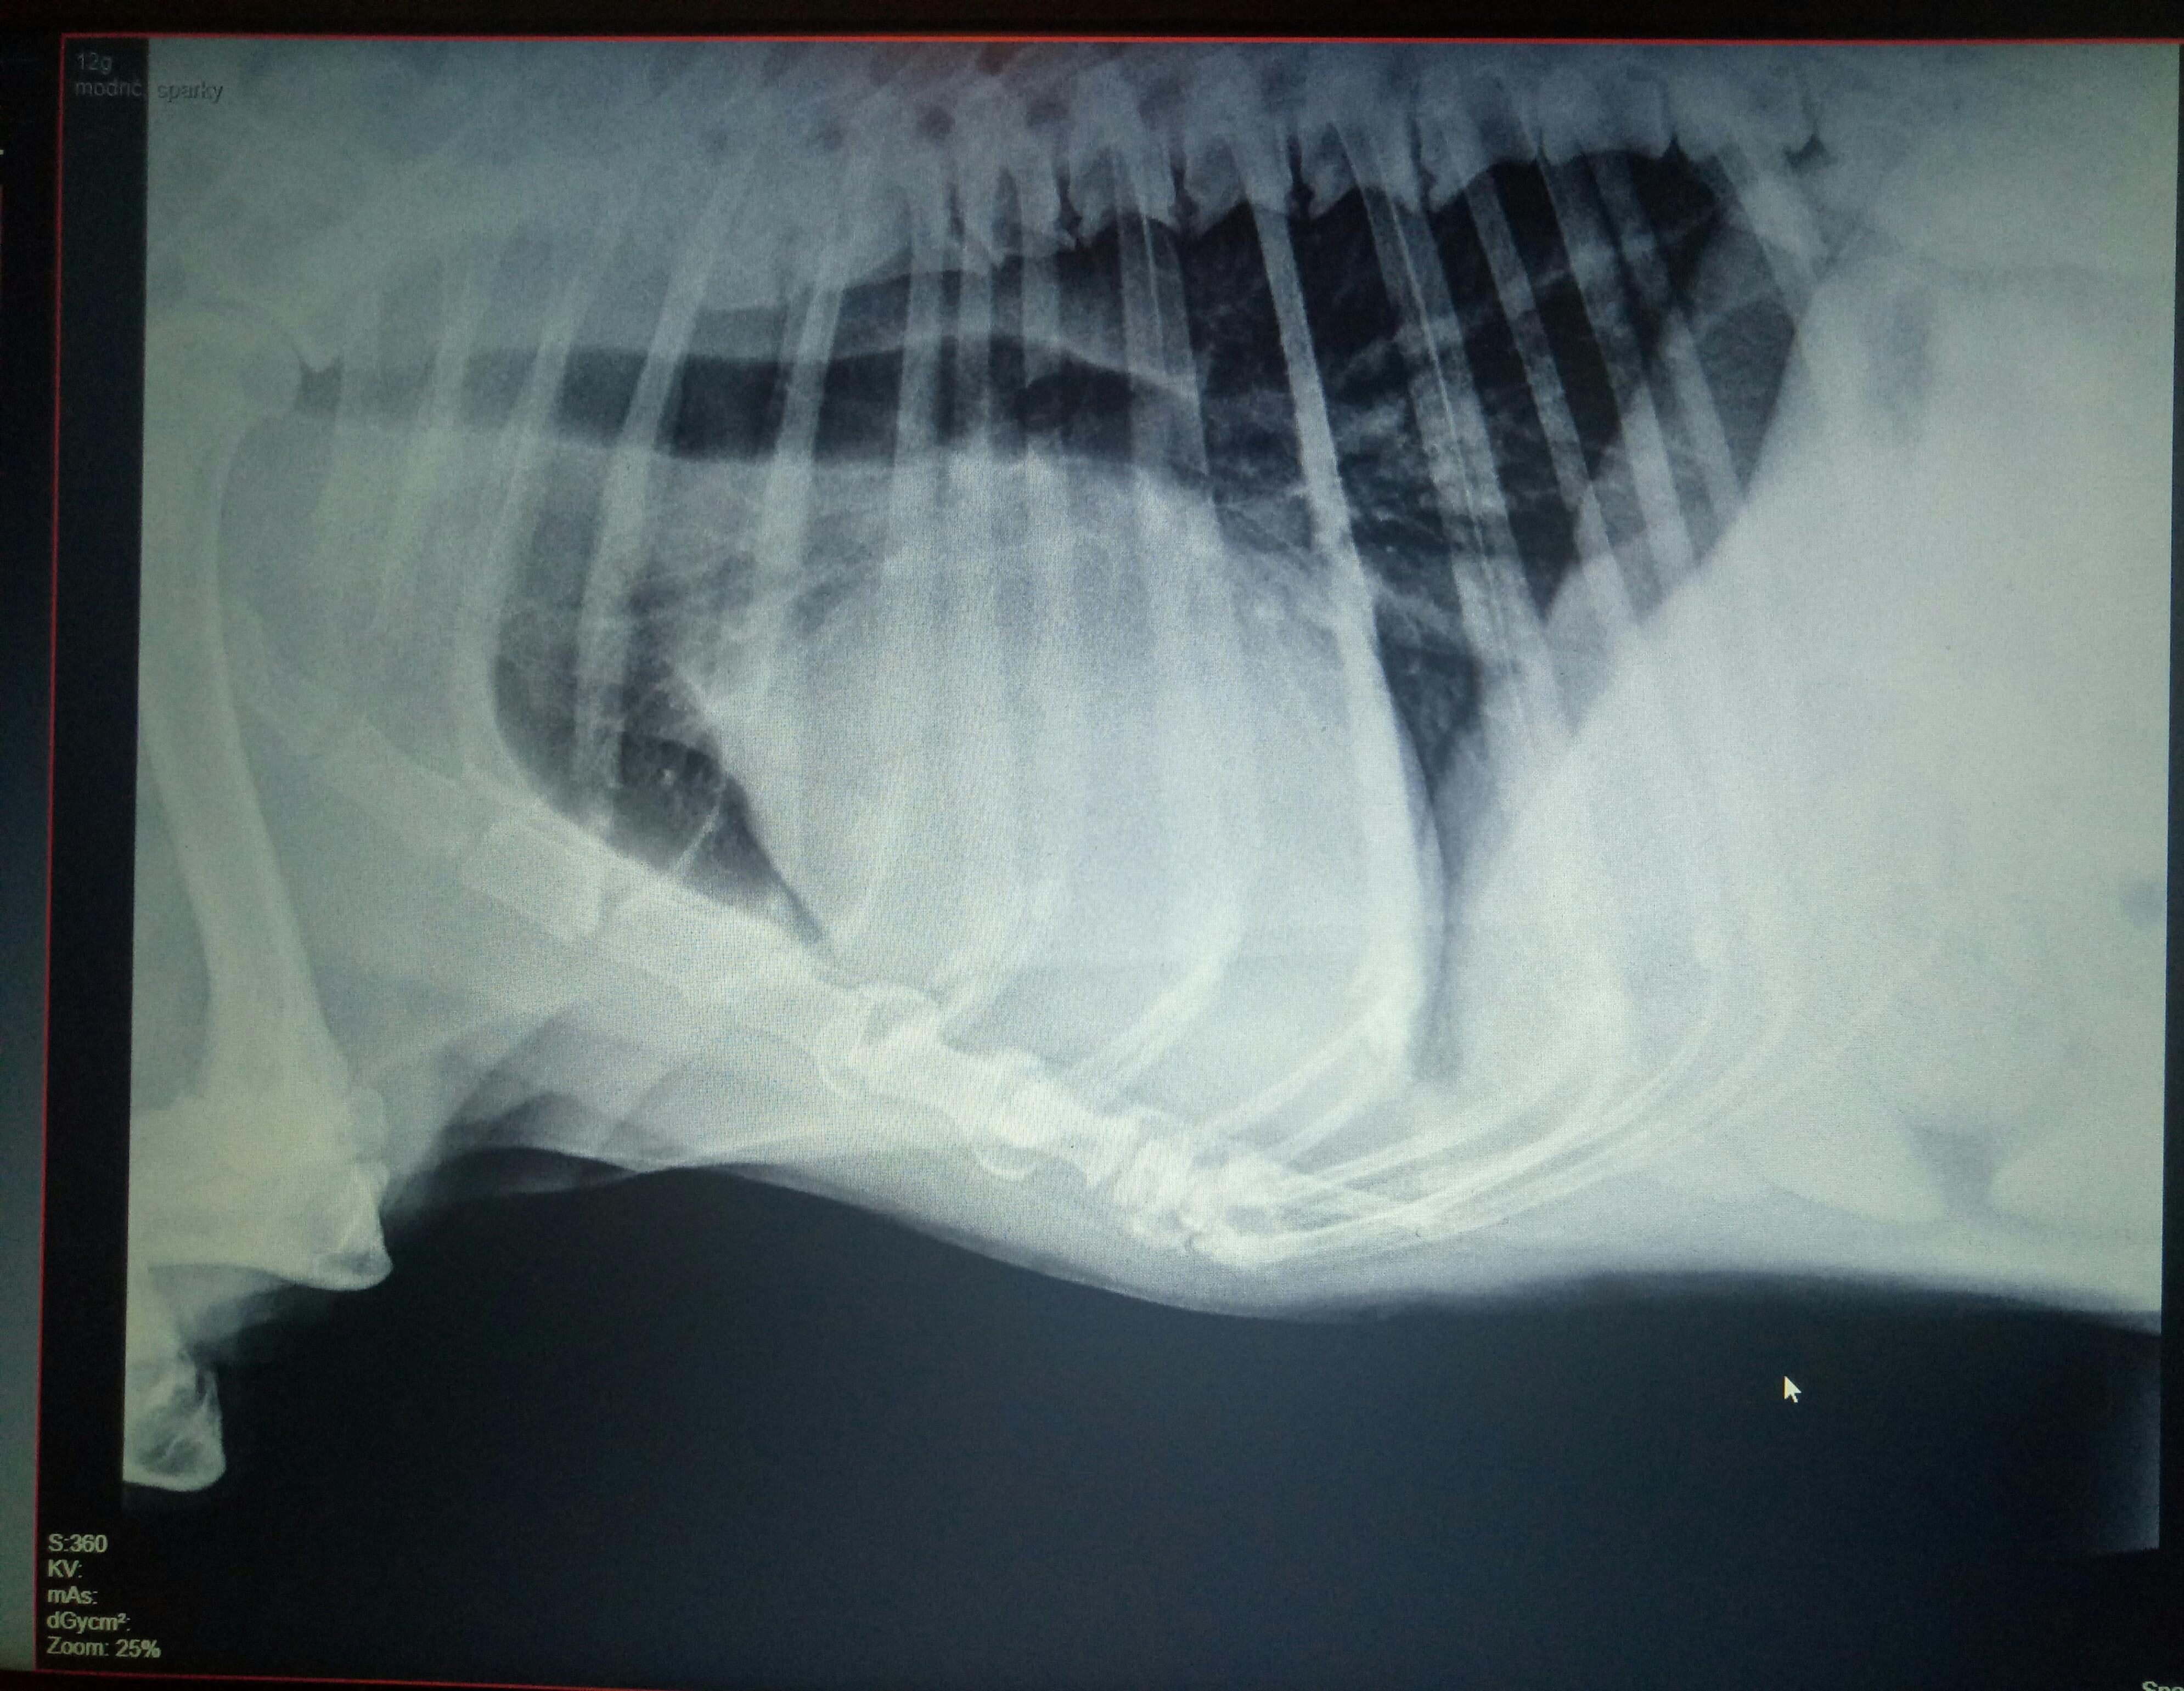

Hello, I took my dog to a vet cause i noticed changes in his behaviour: he pants a lot, can't calm down at night and gets very anxious, caughs daily but not very often and he gets tired at walk a lot sooner than before(walks are now 20mins max). He isn't lethargic and has great appetite. The vet did cardio exam, but i wanted second opinion cause i wasn't very satisfied with whole exam and his opinions cause it's not his area of expertice. He said all is well and doesn't require any treatment.

Thank you for submitting your question regarding Sparkie. It is difficult to say with only one view, but I think that his heart looks enlarged on the x-ray. His trachea also appears elevated. This can cause coughing. Did he have any blood work performed to look for internal abnormalities? I would also evaluate his joints and mobility as this can be a significant source of pain in an older dog. It is worth seeking a second opinion if you are not happy with his exam. You know your dog. I hope this information helps!